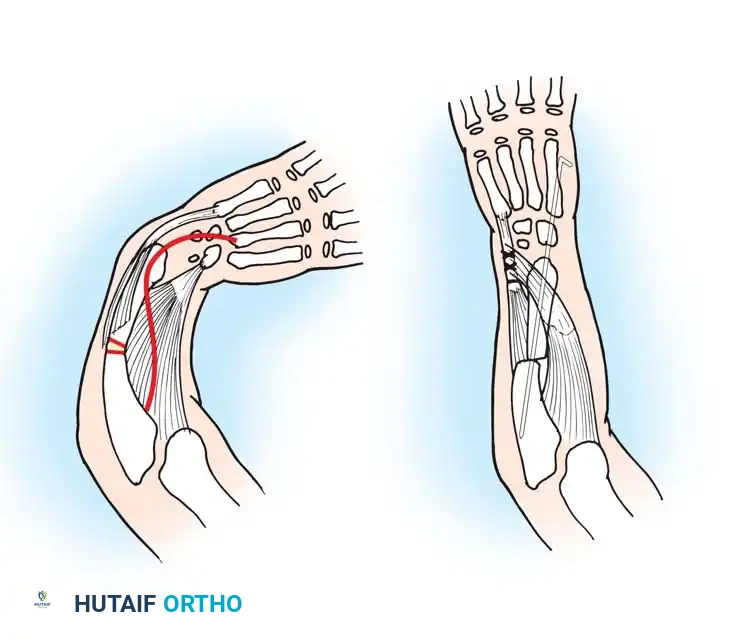

Associated Surgical & Radiographic Imaging